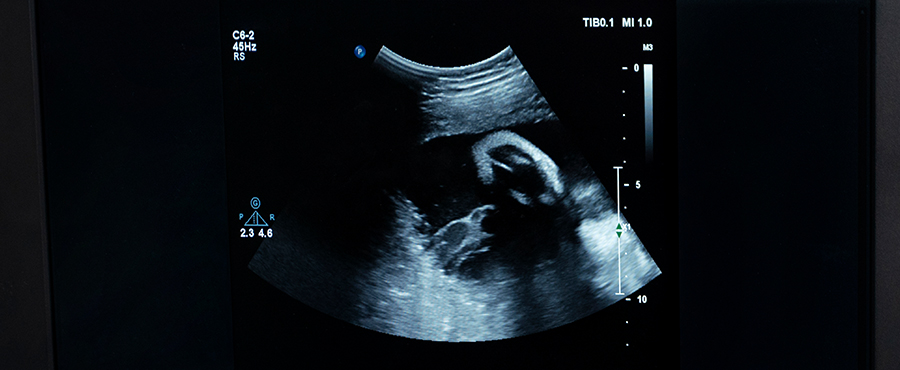

At Hi-Tech Diagnostics, our Scanning Department provides a wide range of imaging services including Abdomen & Pelvis, Obstetric, Breast Ultrasound, Thyroid & Neck, Doppler, and Genitourinary Scans.

Each scan is performed by expert radiologists, ensuring precise diagnostics for timely care.